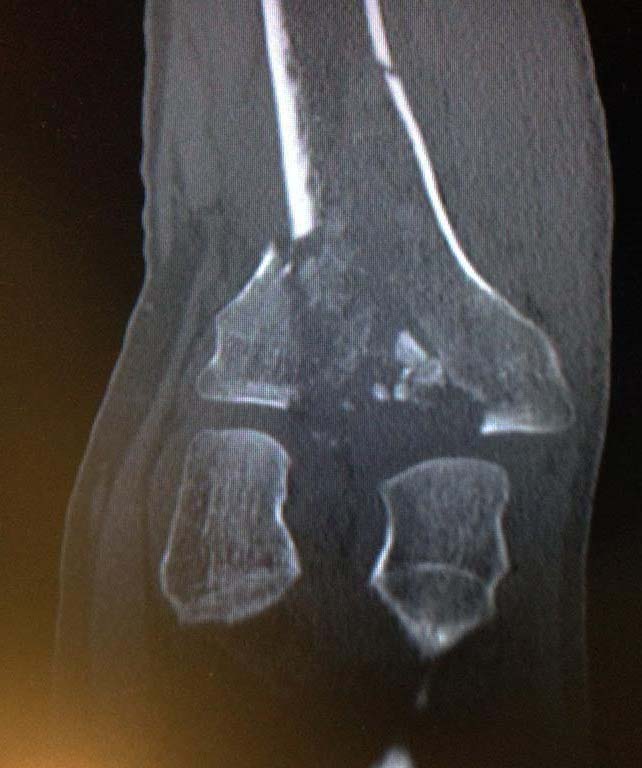

Fractura de meseta tibial Schatzker tipo VI

Fractura de meseta tibial Schatzker tipo VI, resuelta con placa y tornillos por un doble abordaje anterolateral y posteromedial. Se consigue una superficie articular equilibrada y un balance articular completo del paciente (Dr. Cebreiro).